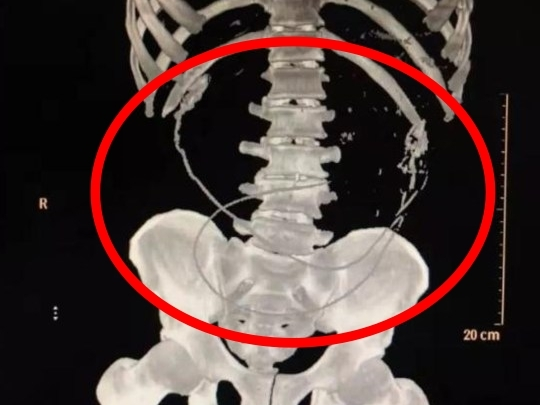

의료진이 원인을 파악하기 위해 CT촬영을 해본 결과, 환자의 배 안에서 장어 두 마리가 꿈틀거리면서 복통을 유발하고 있었다. 더불어 혈액검사 결과 환자의 박테리아 감염이 심각한 수준이었다.

남자는 평소 극심한 만성 변비로 극심한 불편을 겪고 있었다. 그러다 장어가 변비를 완화하는 데 도움이 된다는 민간 요법을 전해들은 것이다. 이에 길이가 50cm에 달하는 살아있는 장어 두 마리를 꿀꺽 삼켰지만 변비를 고치지 못한데다 엄청난 복통이 찾아왔다.

의료진은 "몸 안에 들어간 장어들이 환자의 장기를 깨물었다. 또한 장기 사이를 비집고 다닌 탓에 출혈이 심각한 상태였다. 또한 박테리아 감염도 있었다."고 당시 환자의 상황을 전했다.